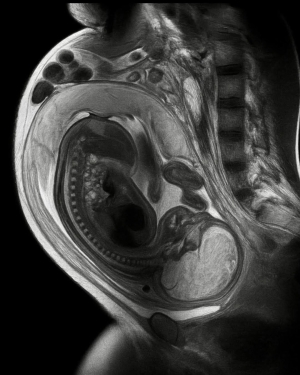

Descoperire epocală dintr-un plan divin al creatiei: Celulele fătului trec prin placentă și vindecă bolile mamei. Celulele mamei trec la făt și se instaleaza in creier permanent

Oamenii de știință au examinat creierele a 59 de femei după decesul acestora, cu vârste cuprinse între 32 și 101 ani. La 63% dintre ele, au descoperit ADN-ul fiilor lor răspândit în diferite regiuni ale creierului. Celulele au călătorit din uter, prin sânge, au trecut de bariera care, în mod normal, împiedică pătrunderea materialului străin în creier și s-au stabilit acolo. Cea mai în vârstă femeie care încă mai avea celule ale fiului său în creier avea 94 de ani.

Transferul începe încă din a 7-a săptămână de sarcină. Celulele tale trec prin placentă în corpul mamei tale. Ale ei trec în al tău. Un studiu a descoperit că o mamă încă mai avea celule ale fiului său în sânge la 27 de ani după naștere. După naștere, între 50 și 75% dintre femei poartă celulele copilului lor. În timpul sarcinii, până la 6% din ADN-ul din sângele unei femei provine de la copil.

Când inima unei mame este afectată în timpul sau după sarcină, celulele copilului se deplasează către zona afectată, se atașează și se transformă în celule cardiace care bat, în căptușeala vaselor de sânge și în mușchi. Insuficiența cardiacă legată de sarcină are o rată de recuperare spontană de 50%, mai bună decât orice alt tip. Echipa de la Mount Sinai care a realizat cercetarea consideră că celulele bebelușului repară inima mamei din interior.

Datele privind cancerul sunt surprinzătoare. Un studiu a comparat femeile sănătoase cu femeile cu cancer de sân. 85% din grupul sănătos încă purta celulele copiilor lor. Doar 64% din grupul cu cancer de sân le avea. Asta înseamnă o probabilitate de aproximativ 4 ori mai mică de a face cancer de sân dacă ai păstrat acele celule. Teoria actuală este că ele "patrulează" în organism și prind celulele canceroase înainte ca acestea să crească.

Un studiu din 2022 a descoperit că, în creierul în dezvoltare, celulele mamei controlau celulele imune ale creierului, împiedicându-le să taie prea multe conexiuni între celulele creierului. Celulele mamei tale au ajutat la conectarea creierului tău înainte de a te naște. Și acest lucru se acumulează de-a lungul generațiilor. O femeie poate purta celule de la copiii ei, de la propria mamă și chiar de la sarcinile pe care mama ei le-a avut înaintea ei. Trei generații de celule de la persoane diferite, care trăiesc în interiorul unui singur corp. Există un plan divin intenționat și coregrafiat pentru viață.